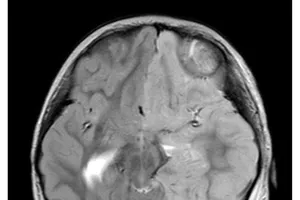

Hội chẩn từ xa với các bác sĩ Đài Loan phẫu thuật thành công cho bệnh nhi bị động kinh Y tế - Sức khỏe 13/11/2023 11:06